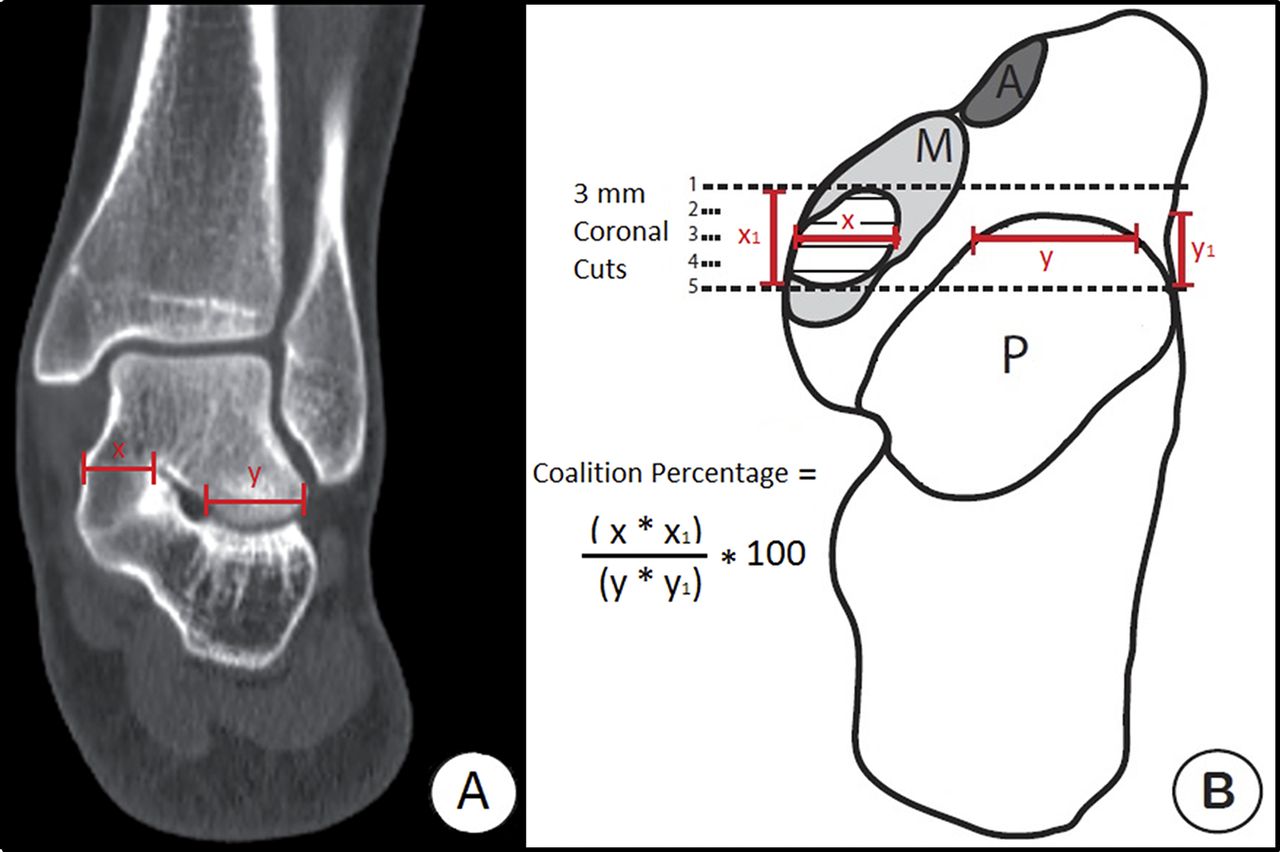

From www.researchgate.net

Drunken waiter sign of talocalcaneal coalition. Download Scientific Shoe Inserts For Tarsal Coalition Tarsal coalition is a common congenital condition caused by failure of embryonic segmentation leading to abnormal coalition 2 or more of the tarsal bones. Shoe inserts and ankle strengthening exercises can also help. Custom molded shoe inserts (often referred to as orthotics) can help alleviate pain by distributing weight away from the joint. Orthotic devices — arch supports, shoe inserts. Shoe Inserts For Tarsal Coalition.